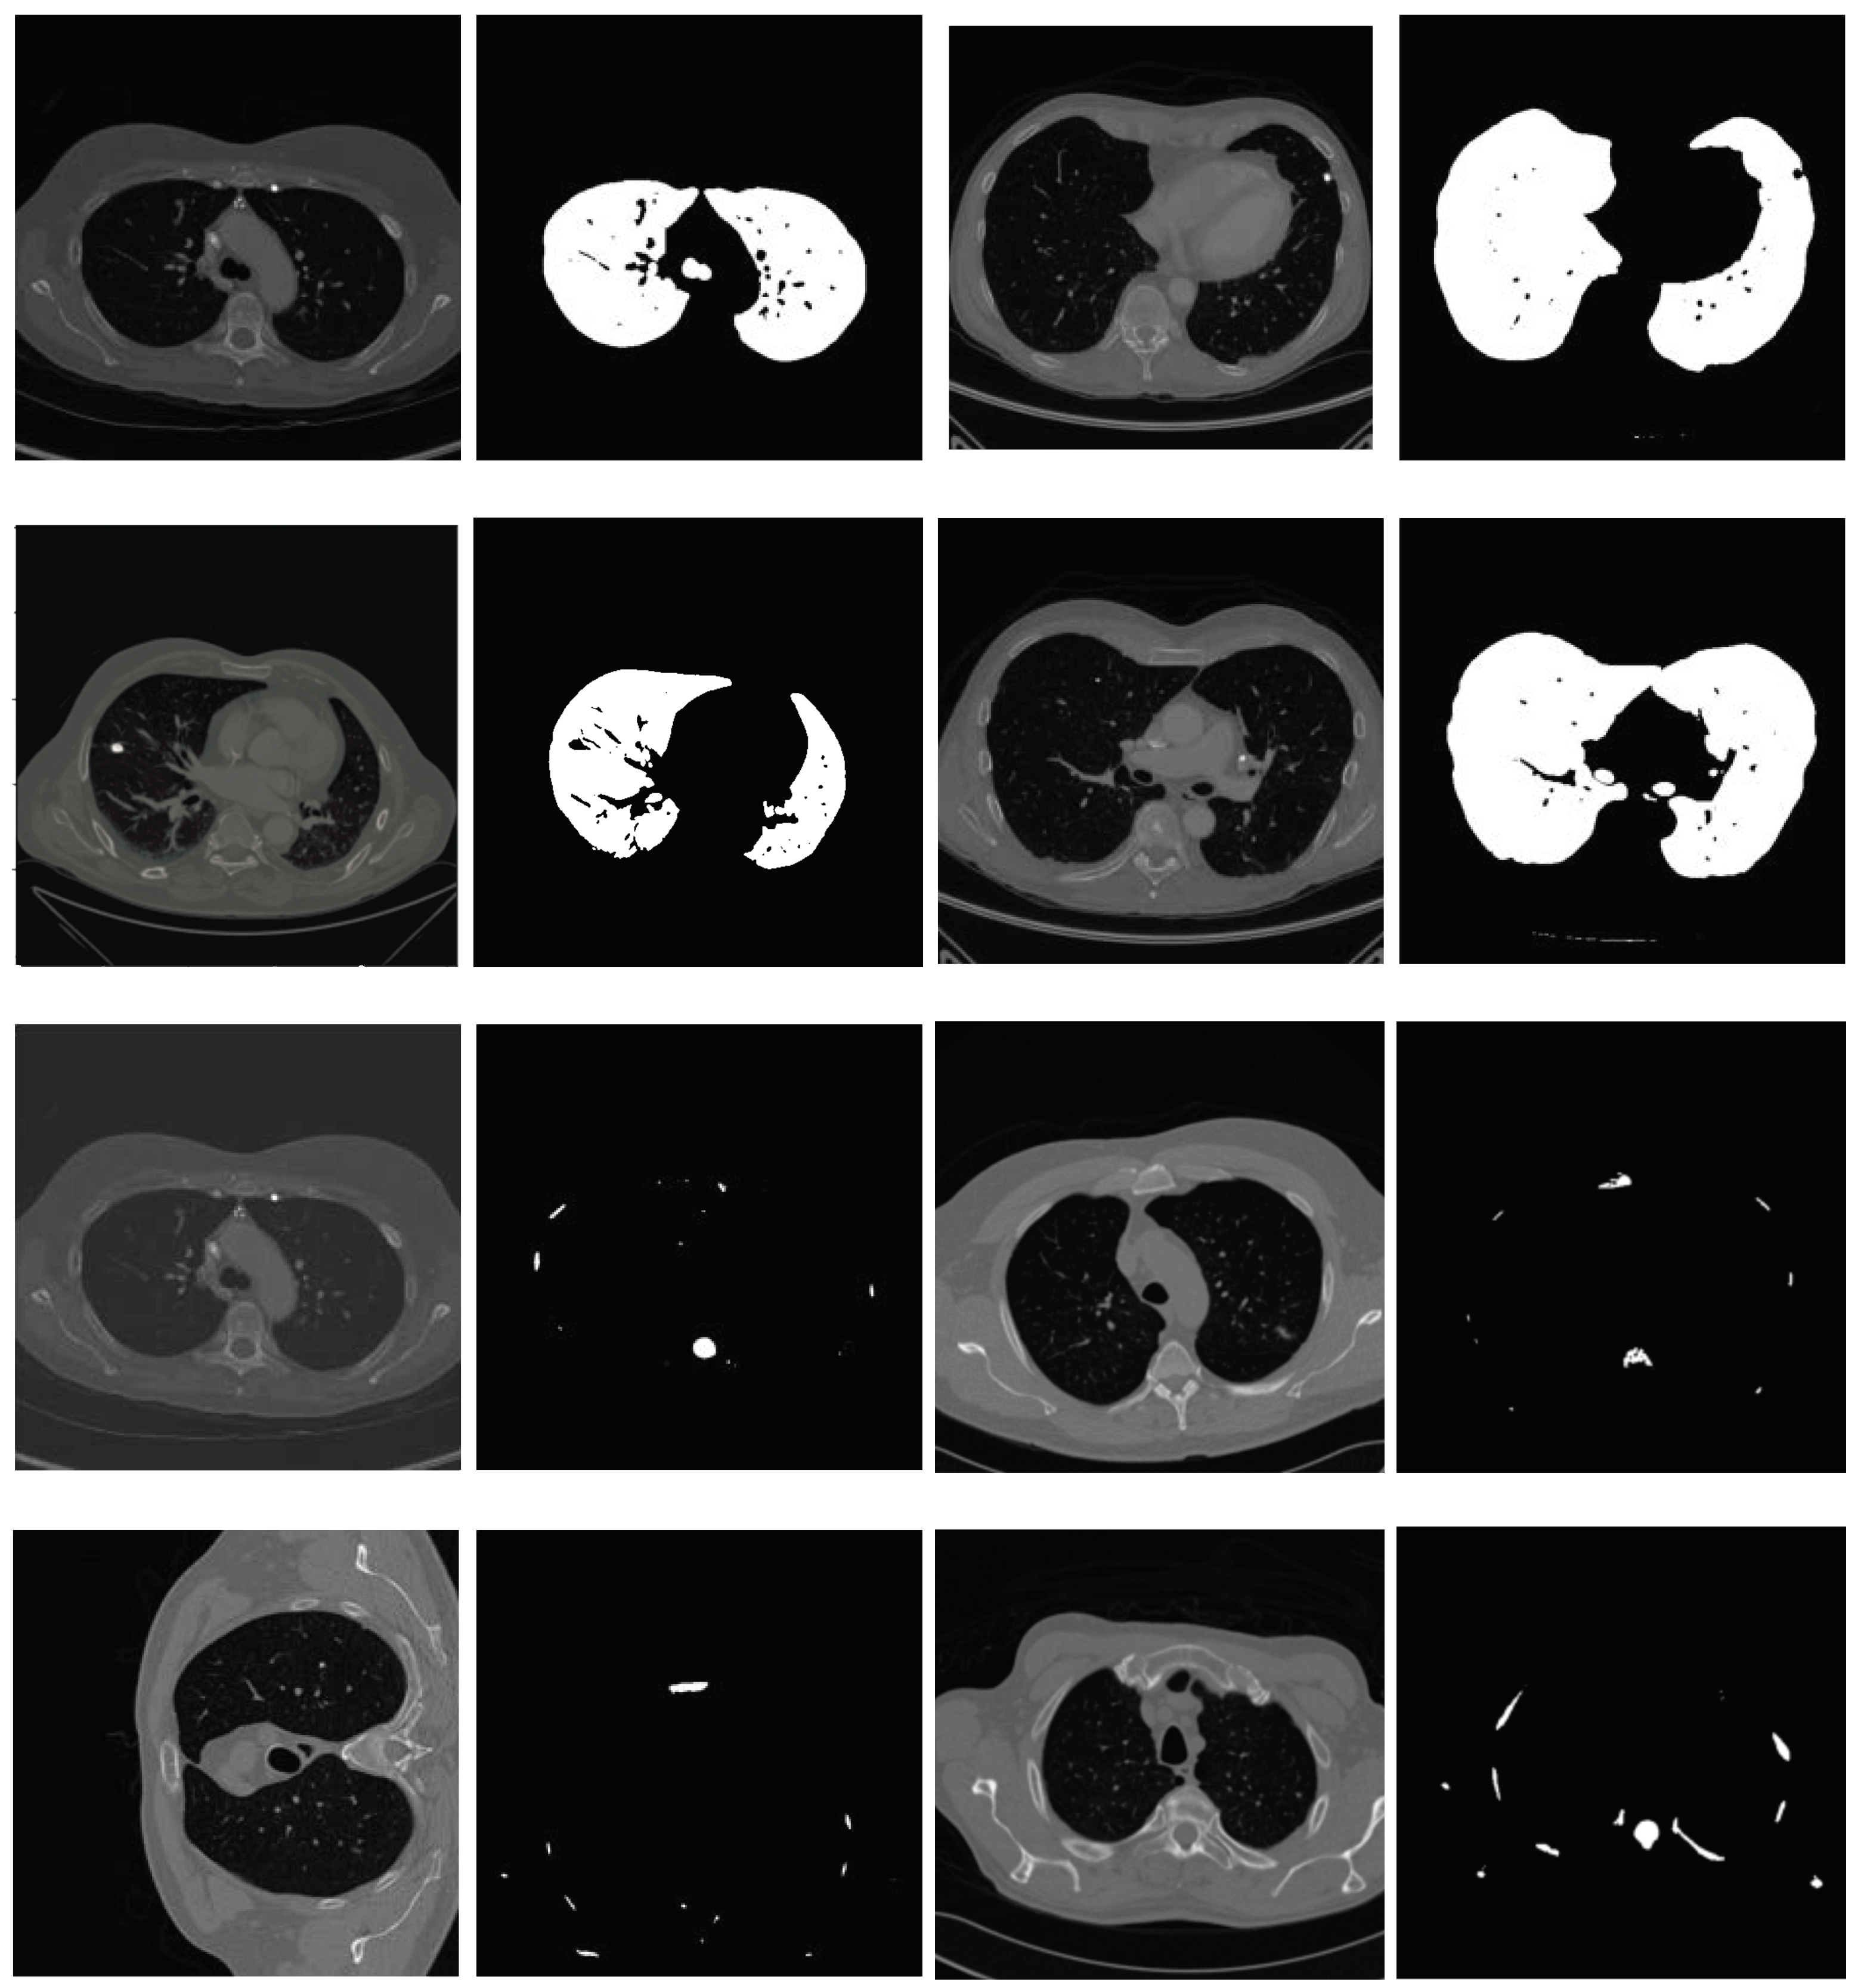

2.2.1. Segmentation in Lung Window

2.2.2. Segmentation in Mediastinal Window